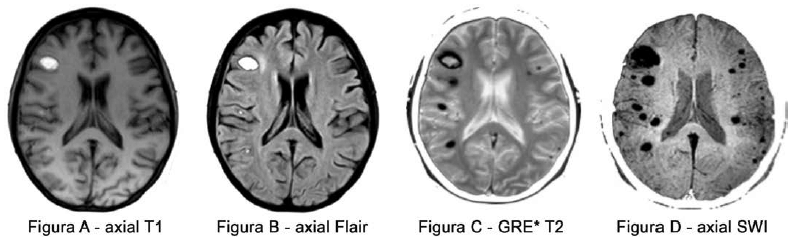

Um paciente de 22 anos, com estado de imunodepressão, foi internado com febre, crises convulsivas e quadro respiratório a esclarecer. É submetido a exame de ressonância magnética que revelou as alterações a seguir (Figuras A a D). No estudo laboratorial do líquor, houve o isolamento de um fungo.

Baseado nas imagens de ressonância magnética, assinale a provável doença fúngica do paciente.